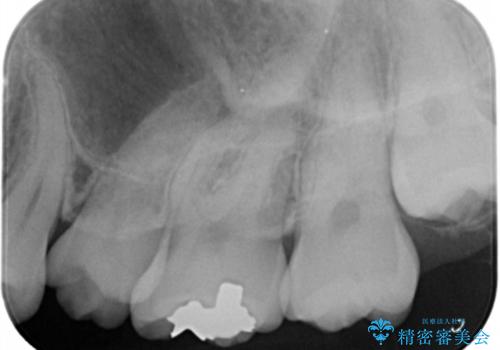

- 奥歯の歯が黒いとの事で来院された患者様です。

頬側の歯の面も粗造になっていたので、インレーではなくジルコニアクラウンでの治療となりました。